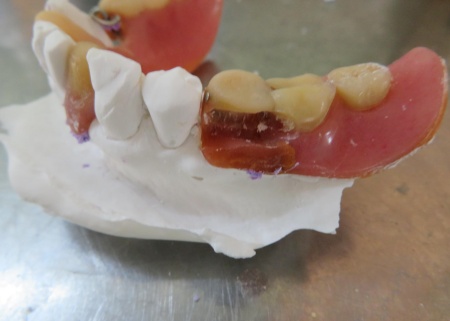

| カウンセリング・診断結果 | 拝見したところ、左下の歯には部分入れ歯が装着されていましたが、入れ歯を支える金属バネ「クラスプ」が破損しており、入れ歯をしっかりと固定することができなくなっていました。 クラスプが折れた状態では入れ歯が安定せず、食事中などに外れやすくなります。 また、破損した入れ歯を使い続けると、入れ歯が歯茎にこすれて傷が付いたり、顎の関節や残っている歯に過度な負担がかかったりするリスクがあります。 以上のことから、折れたクラスプを作り直す必要があると診断しました。 |

| 行ったご提案・治療内容 | 今回は、破損していたクラスプを新しく作り直し、入れ歯を修理する方法を提案しました。 これまでも同様の修理を行っているため、患者さまも修理の流れをよく理解されています。 入れ歯を修理する場合は、入れ歯をお預かりして数日から1週間ほどお時間をいただくのが一般的ですが、当院では歯科医師が院内でクラスプを作製できるため、約1時間で修理をすることが可能です。 ただ長期的な使用状況によっては、再度調整や修理が必要になることもあります。 修理方法のメリットとデメリットをお伝えし、同意いただきました。 まずは入れ歯を装着した状態で型取りを行い、模型を作製します。 完成した模型に入れ歯を装着し、クラスプを固定する場所を削りました。 クラスプ用のワイヤーは手作業で曲げながら、残っている歯の形態や傾きに合わせて精密に調整します。 その後、完成したクラスプを入れ歯に取り付けたうえで装着していただき、実際にお口の中で安定性や装着感を確認しました。 最後に、噛み合わせや着脱のしやすさ、見た目に問題がないかなどを確認し、治療を終了しています。 |